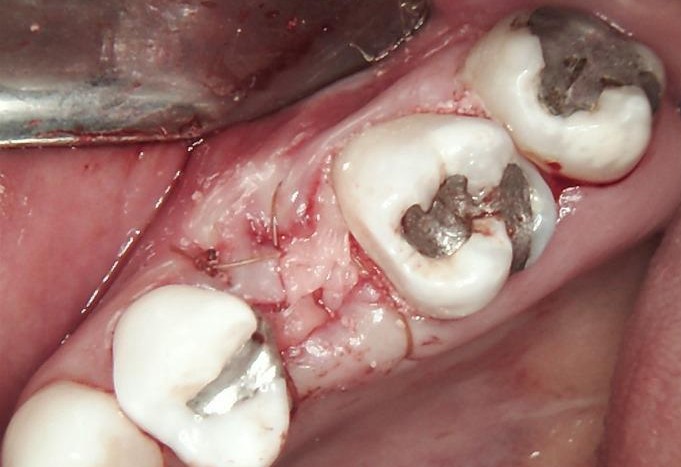

HEALING STAGE

During the healing phase, soft tissue maturation and integration were closely monitored. Soft tissues were carefully managed, using the Free Gingival Graft technique, which allowed for enhancing keratinised tissue and improving peri-implant tissue stability.

A healing cap was placed to guide soft-tissue contouring and support optimal formation of the emergence profile.